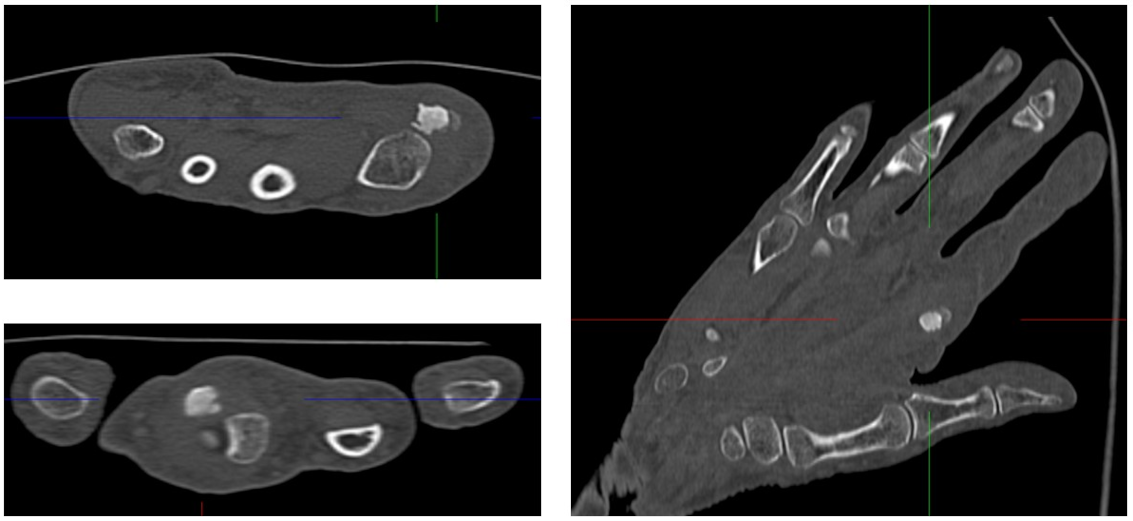

We performed a radiographic examination of the affected hand, followed by a contrast-enhanced CT scan. Based on the imaging findings, avascular necrosis of the sesamoid bone at the MCP joint was suspected (Figure 2 [Fig. 2], Figure 3 [Fig. 3] and Figure 4 [Fig. 4]).

Figure 3: Preoperative Computed Tomography (CT) of the right hand